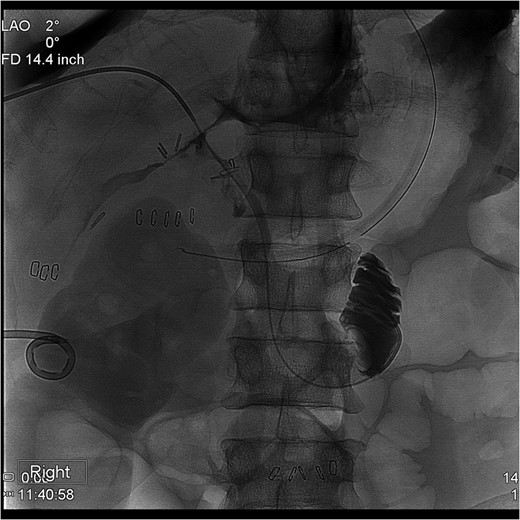

The PTC study confirmed the presence of a completely transected duct, and, fortunately, the ductal injury was traversed with a wire with entry into the distal ductal orifice and into the duodenum (Figs 4–6). Following the procedure, the patient was taken directly to the operating room for open surgical repair.

Percutaneous Transhepatic Cholangiogram with proximal contrast extravasation. Note adjacent surgical clips.